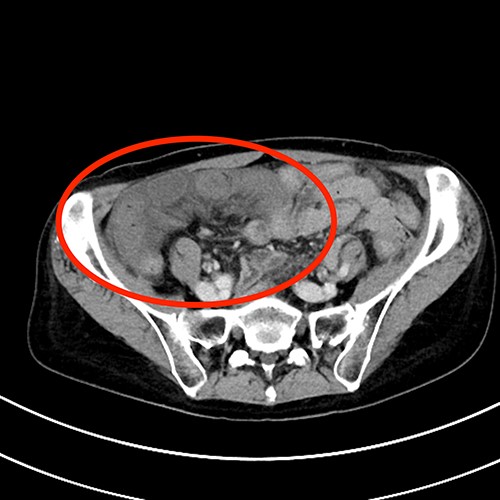

A 66-year-old female without any history of abdominal surgery or medical problems experienced a sudden intensive lower abdominal pain at 4 a.m. while sleeping. Her family contacted the emergency medical system, and she was transported to our emergency department (ED). Her vital signs at the ED showed tachypnea, but no signs of fever. On physical examination, her abdomen was soft, but there was a rebound tenderness in her right lower abdomen. No abnormalities were found in the laboratory tests, except for an elevated creatinine kinase of 250 IU/L (reference range: 41–153 IU/DL). Contrast-enhanced computed tomography revealed closed loop bowel obstruction in the right lower abdomen. (Fig. 1) Since the patient had a virgin abdomen, a diagnosis of internal hernia secondary to physiological intra-abdominal adhesions was made and laparoscopic examination was initiated 5 h after the onset of abdominal pain.

Contrast-enhanced abdominal computed tomography findings. Small bowel loops with caliber change and edematous mesentery are in the right lower abdomen.